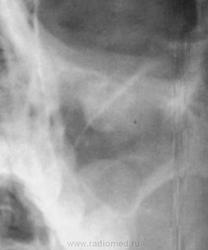

Кисты левой верхнечелюстной пазухи.

Полициклическое утолщение слизистой - картина хронического гайморита.